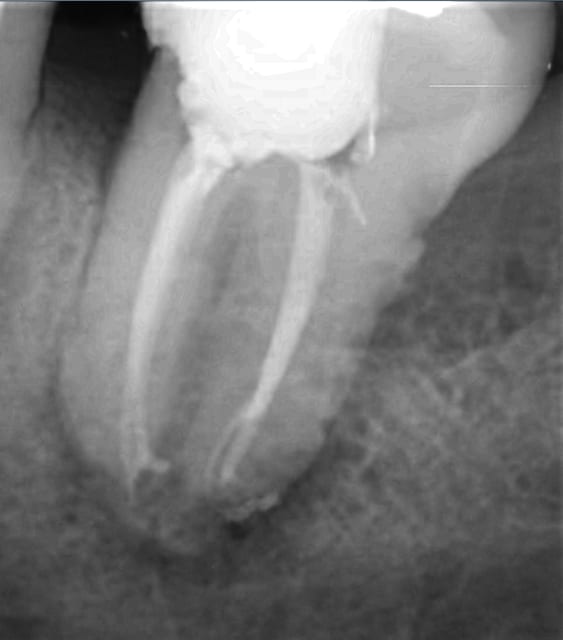

Celle de ce soir :

Par contre j'ai souvent des douleurs importantes lors de l'alésage sur les dents de ce type : longues à racines fines. Je ne comprends pas malgré l'intrapulpaire, les patients ont parfois super mal. SI quelqu'un sait ce qui peut être en cause?

--

www.dentaltradegroup.com